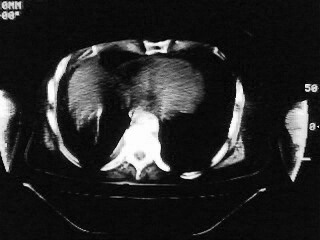

以下是引用随光逐影在2009-2-10 0:07:00的发言:[br]1)右肺放射性肺炎并节段性肺不张?请结合相关病史。2)右侧胸膜肥厚、粘连。3)心包膜增厚(或心包少量积液)。